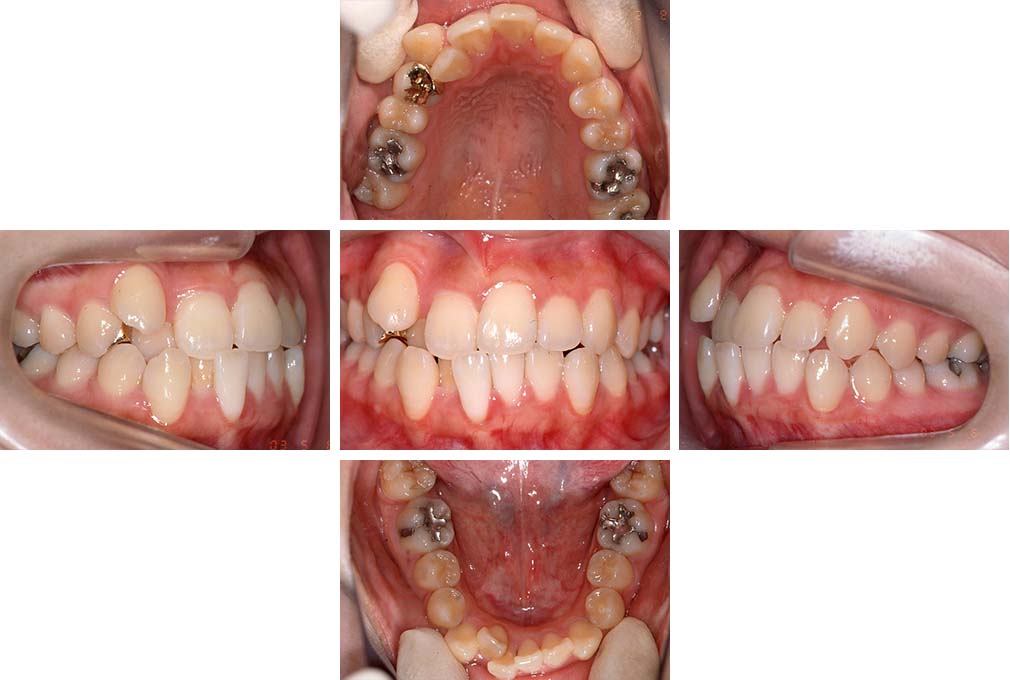

CASE:01

叢生を伴う骨格性上顎前突

初診時年齢 15歳10カ月

性別 男性

治療費の目安 約75万円程度(治療開始時)

上顎前歯の前突と叢生を主訴として来院された。大臼歯関係は左右側ともにⅡ級で上顎の方が前方に位置していた。叢生を伴う骨格性上顎前突と診断し、上下顎小臼歯抜歯を行っていただきマルチブラケット装置に顎外固定装置を併用して動的治療を行った。顎外固定装置や矯正用ゴムの使用など協力状態も良好で、動的治療期間2年0カ月、調整来院20回でマルチブラケット装置を撤去し保定へ移行した。動的治療終了後10年0カ月を経過したが保定移行時とほぼ同様の咬合状態で良好な状態を保っていた。

治療前

15歳10か月

治療後

動的治療期間2年0カ月

18歳5か月

10年経過

動的治療終了後10年0カ月

28歳5か月